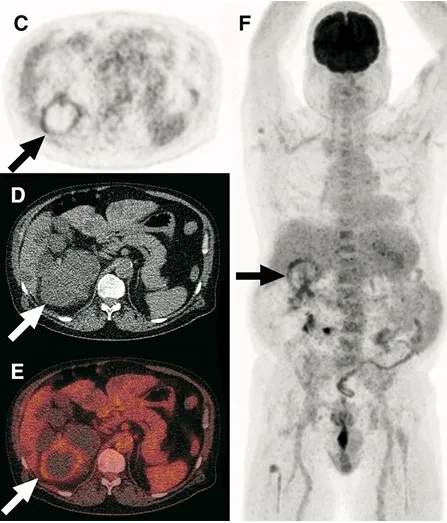

Diálise Peritoneal na Doença Renal Policística: existe algum motivo para não indicar?

Diálise Peritoneal na Doença Renal Policística: existe algum motivo para não indicar?

A DRPAD não é contraindicação à DP — e, na prática, muitos pacientes têm resultados comparáveis à hemodiálise. O “porém” está na mecânica: rins/hepatomegalia podem reduzir tolerância a volumes, aumentar risco de hérnias e extravasamentos, e piorar desconforto respiratório. Com técnica adequada (cateter presternal ou lateral, volumes menores, cicladora noturna e decúbito supino), a maioria das barreiras é contornável. Neste post, revisamos quando a DP é ótima, quando exigir cautela e como ajustar a prescrição para segurança e qualidade de vida.